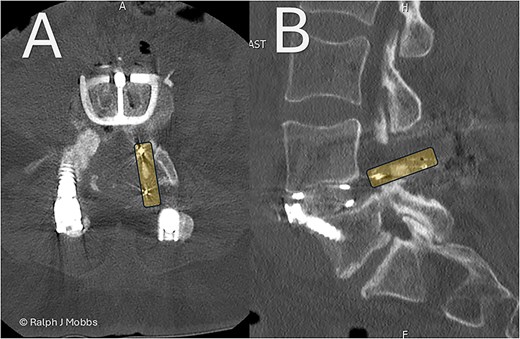

Stage one: anterior lumbar interbody fusion

Day 1 postop ALIF. The PEEK cage can be seen in the canal and paraspinal regions. (A) Axial sequence. (B) Parasagittal sequence.